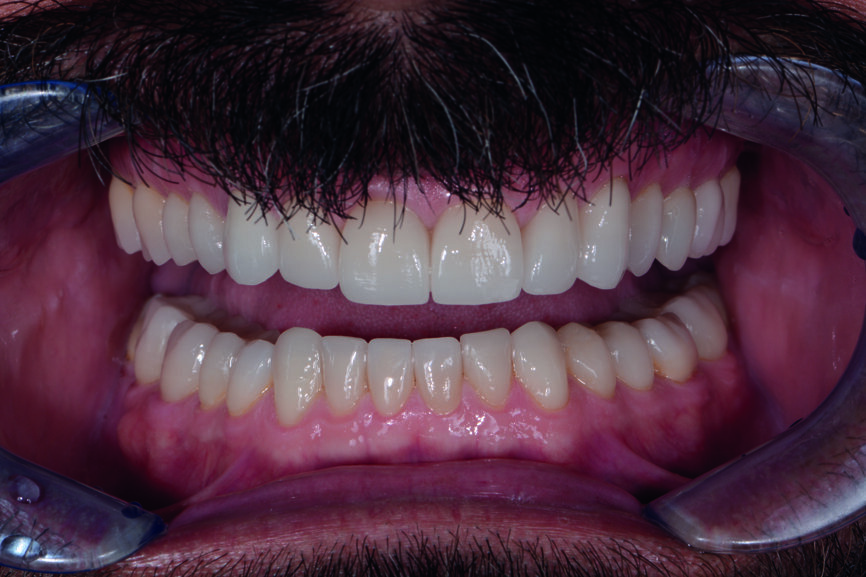

Figs. 13 et 14 : Photographies intraorales après le traitement.

Figs. 16 et 17 : Photos de suivi en janvier 2021 montrant un résultat très stable sans aucun écaillage de la céramique et des avantages mécaniques constants mentionnés par le patient, tels que plus de céphalées de tension

Les couronnes (#11–13 et 21–23) et les facettes (#14–17, 24–27, 31–37 et 41–47) sont collées sur les dents piliers au moyen d’une colle composite photopolymérisable (Futurabond U et Bifix QM, VOCO). Un dispositif équipé d’une lampe LED à haute puissance (Celalux 3, VOCO) est utilisé pour la photopolymérisation (Figs. 11 et 12).

Après l’élimination de l’excès de colle composite, l’occlusion est adaptée et vérifiée à l’aide du système d’évaluation occlusale T-Scan (Tekscan). Une contention amovible en résine acrylique est utilisée pour protéger les restaurations définitives, et celles-ci sont vérifiées six mois plus tard. À ce moment, les restaurations sont toujours stables et ne présentent aucun signe de fracture (Figs. 13–15). Le patient déclare également qu’il n’a plu souffert de maux de tête grâce à cette nouvelle dimension verticale d’occlusion.